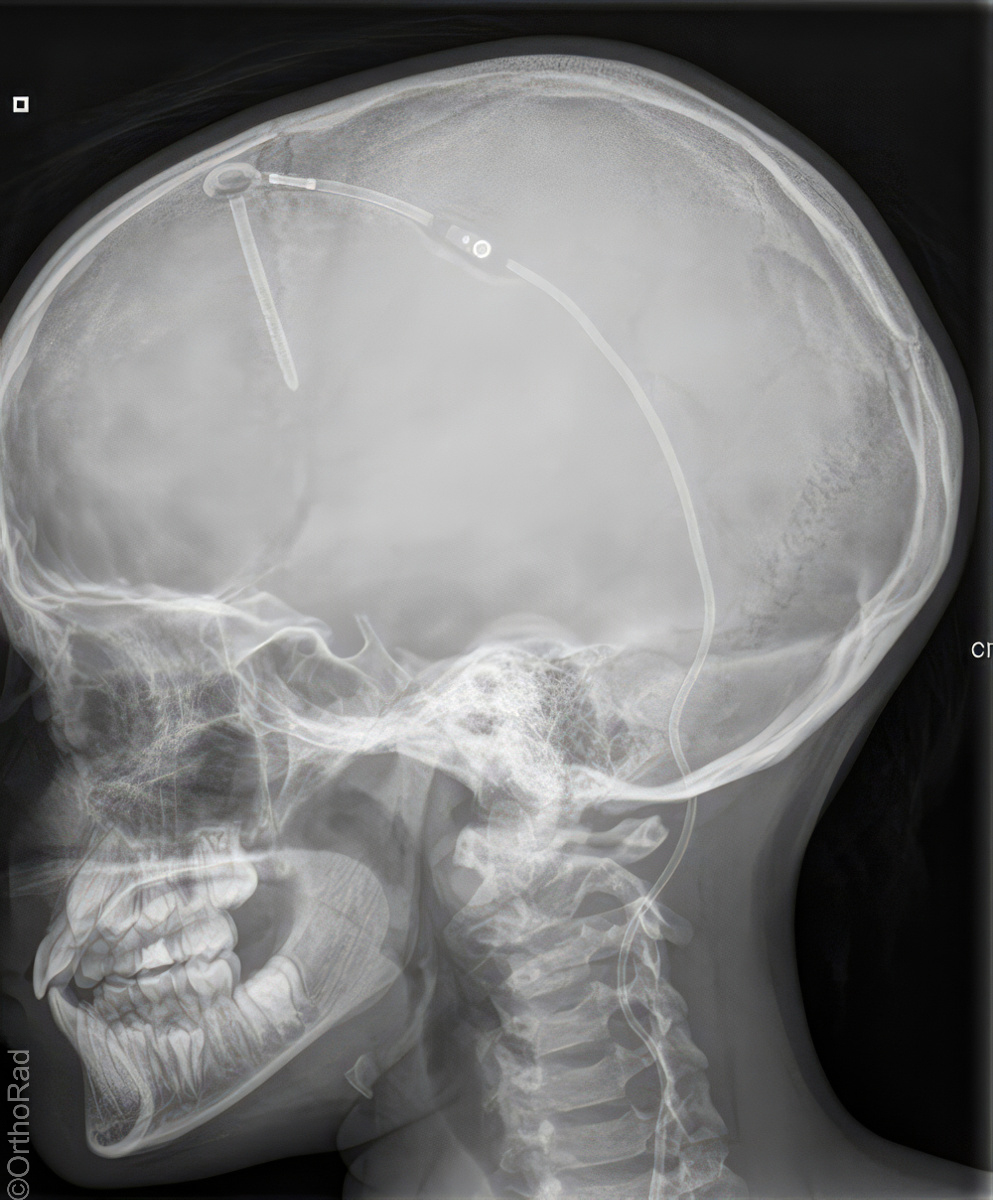

Shuntverlauf

Indikation

Shuntkontrolle

Lagerung

1. Schädel/HWS ap

Patient in Rückenlage, Kinn anziehen lassen, 15° Keil unter den Kopf, so dass Deutsche Horizontale (DH = Frankfurter) senkrecht zum Film steht, Kopf muss seitengleich, symmetrisch gelagert werden.

2. Schädel/HWS seitlich

Patient in Rückenlage, Kopf auf die rechte Seite drehen und Medianebene verläuft parallel zum Tisch, Stirn-Augenbrauen-Linie verläuft senkrecht und die Stirn-Kinn-Punkte verlaufen parallel zur Filmeinblendung. Der Körper dreht sich somit etwas auf die rechte Seite.

3. Thorax/Abdomen

Patient in Rückenlage, Arme am Körper entlang, Beine geschlossen.

4. evtl Becken

Patient in Rückenlage, Beine leicht gespreizt.

Zentralstrahl

Senkrecht auf Objekt, vom Schädel bis Abdomen müssen alle Bilder überlappend sein.

Variante

Abdomen evtl seitlich röntgen, wenn die Shuntlänge 3-4cm unterhalb der Markierung ist (nicht mehr im kleinen Becken) -> Belichtung dann wie seitliche Wirbelsäule.

Anmerkung

Die Stelle (Narbe) an der der Shunt in dem Abdomen verschwindet, muss mit einer Metallkugel etc. markiert werden.